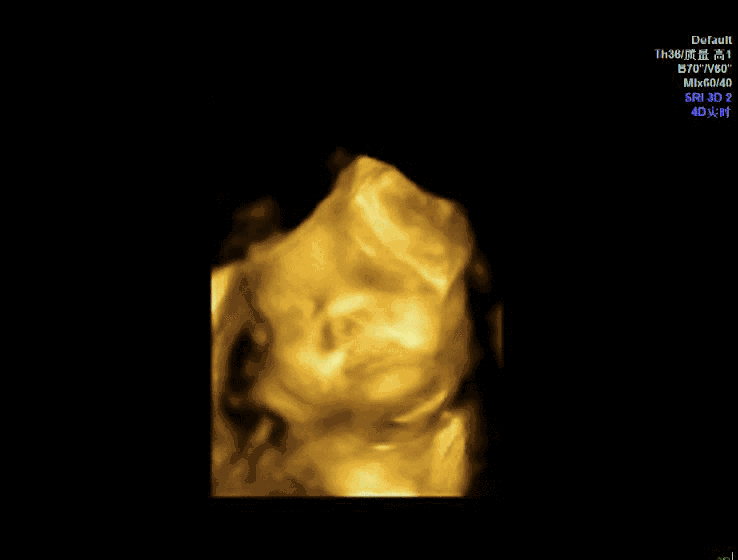

观察婴儿手脚和面部发育情况

倘若使用四维多普勒超声检查时,婴儿处于紧握拳头的时刻,两侧长骨可直观了解到,手脚长度正常且齐全,脊柱未扭曲,五官清晰无异常,而且没有兔唇现象

这些现象表明婴儿的手脚以及脸部发育是正常的,没有异常症状,此外,四维多普勒超声还可以测量婴儿的头围和腹围,可以通过检查更多地了解到婴儿的具体情况。